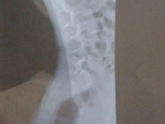

Девочки привет , вот 2 дня назад на рентген обнаружили спина бифида s1 s2 , переживание съедает в интернете посмотрела вообще до паники дошло , была у врача лечится сказала, но у неё наружу ничего не вышло ?♀️???есть которые сталкивались ? ?